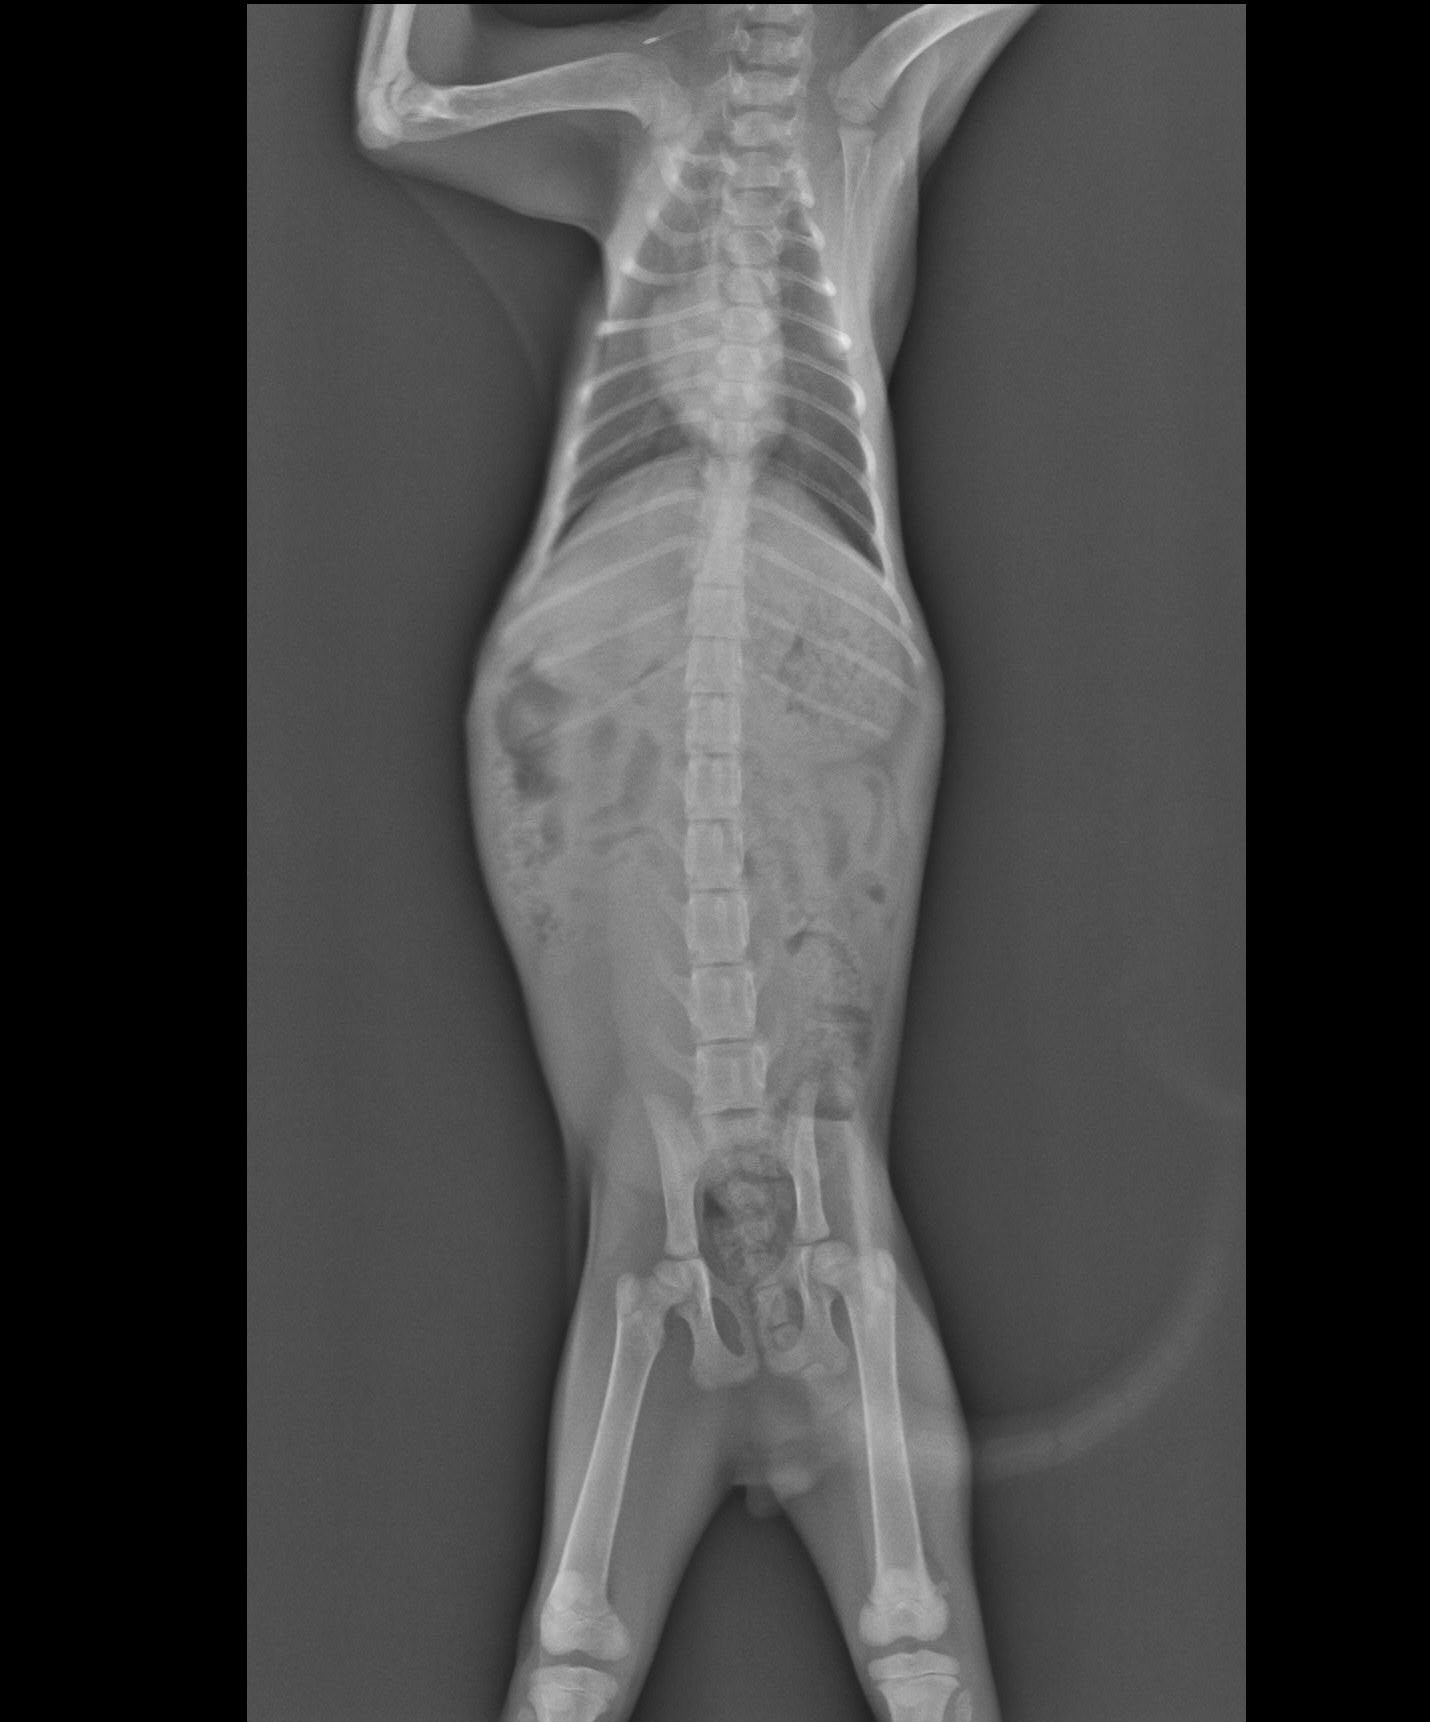

主題: 車禍黑貓 申請者姓名: 張菱予 花色: 申請日期: 2018-07-26 11:35:18 申請者部落格: 申請者臉書網址: http://www.facebook.com/clyanal 所在縣市/合作醫院: 高雄市/小新動物醫院 治療費用: 12150元 需求人數: 26人 已結案 (2024-06-01 13:09:58) 報名人員: 珊珊(已付款)、郁婷(已付款)、lin789 x14(已付款)、Fenny x10(已付款)、 候補人員: 動物病情說明: 晚上十點半在國道十號匝道口看到小黑趴在路中央不能動彈,高速公路上的車在小黑咫尺處疾駛而過,情況非常緊急,暫停路邊等待時機衝上前去把滿臉是血的他帶離路面!仔細查看發現小黑眼睛鼻子有出血狀況,四肢有反應但無力,僅能微微晃動,研判受到不小的撞擊!儘速送往小新動物醫院,醫生做初步觸診時小黑並無太大反應,雙眼緊閉,但是仍有意識、心跳,但有失溫狀況,趕緊給予保溫和輸液治療,先把生命跡象穩定下來再進行後續治療! 動物近況說明: 小黑到院後先穩定生命跡象,輸液治療並使用降腦壓藥物治療腦傷。接著照X光檢視是否有骨折,所幸小黑骨頭並未受到傷害。治療初期小黑並無法正常行動,僅能將頭微微抬起進食,但持續給藥輸液治療兩週後能正常行走,研判已無生命危險,故接出院自行中途照護。在此感謝各位捐款人,讓求生意志強烈的小黑能夠得到良好的醫療照顧!